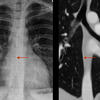

coronal CT